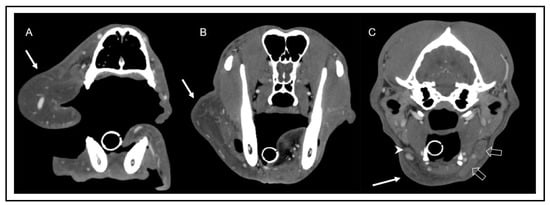

Figure 5. Transverse computed tomographic images after indirect lymphography with subcutaneous injection of contrast medium into the rostral aspect of the bilateral lips one minute after injection. Images were obtained at the level of the rostral nasal cavity (A), frontal sinus (B), tympanic bulla (C), and atlas (D). Multiple well enhanced lymphatic vessels (arrows) can be identified in the left lip (A), continuing caudoventrally (B), and draining into the left mandibular lymph nodes (open arrow in image (C)) and the left medial retropharyngeal lymph node (arrowhead in image (D)). Note the scant volume of contrast media extending along the facial planes (double-headed arrow in image (A)). On the right side, lymphatic vessels could not be identified, and there was no contrast enhancement of the right mandibular and medial retropharyngeal lymph nodes.

Finally, an indirect CT lymphography was performed under general anesthesia with iodinated contrast medium. A total amount of 10 mL of contrast media (Ioversol, Optiray 300 mg I/mL, Guerbet) was injected subcutaneously into the rostral aspect of the lip on both sides over a period of two minutes, followed by a massage of that area of the same duration. Thirty minutes after the application of contrast agent, a total of seven post-injection scans were performed.

Immediately after injection, multiple lymphatic vessels were visualized on the left side, draining to the ipsilateral mandibular and medial retropharyngeal lymph nodes. On the right side, a scant volume of contrast media was identified, extending caudally from the injection site along the facial planes. No lymphatic vessels or lymph node enhancement could be appreciated on the right side in any scan (Figure 4 and Figure 5). In summary, there was absent lymphatic drainage of the right upper lip/cheek, and the small right mandibular lymph nodes were considered to be hypoplastic. In light of these findings, the most likely diagnosis was a primary lymphedema due to absent or malfunctioning lymphatic vessels.